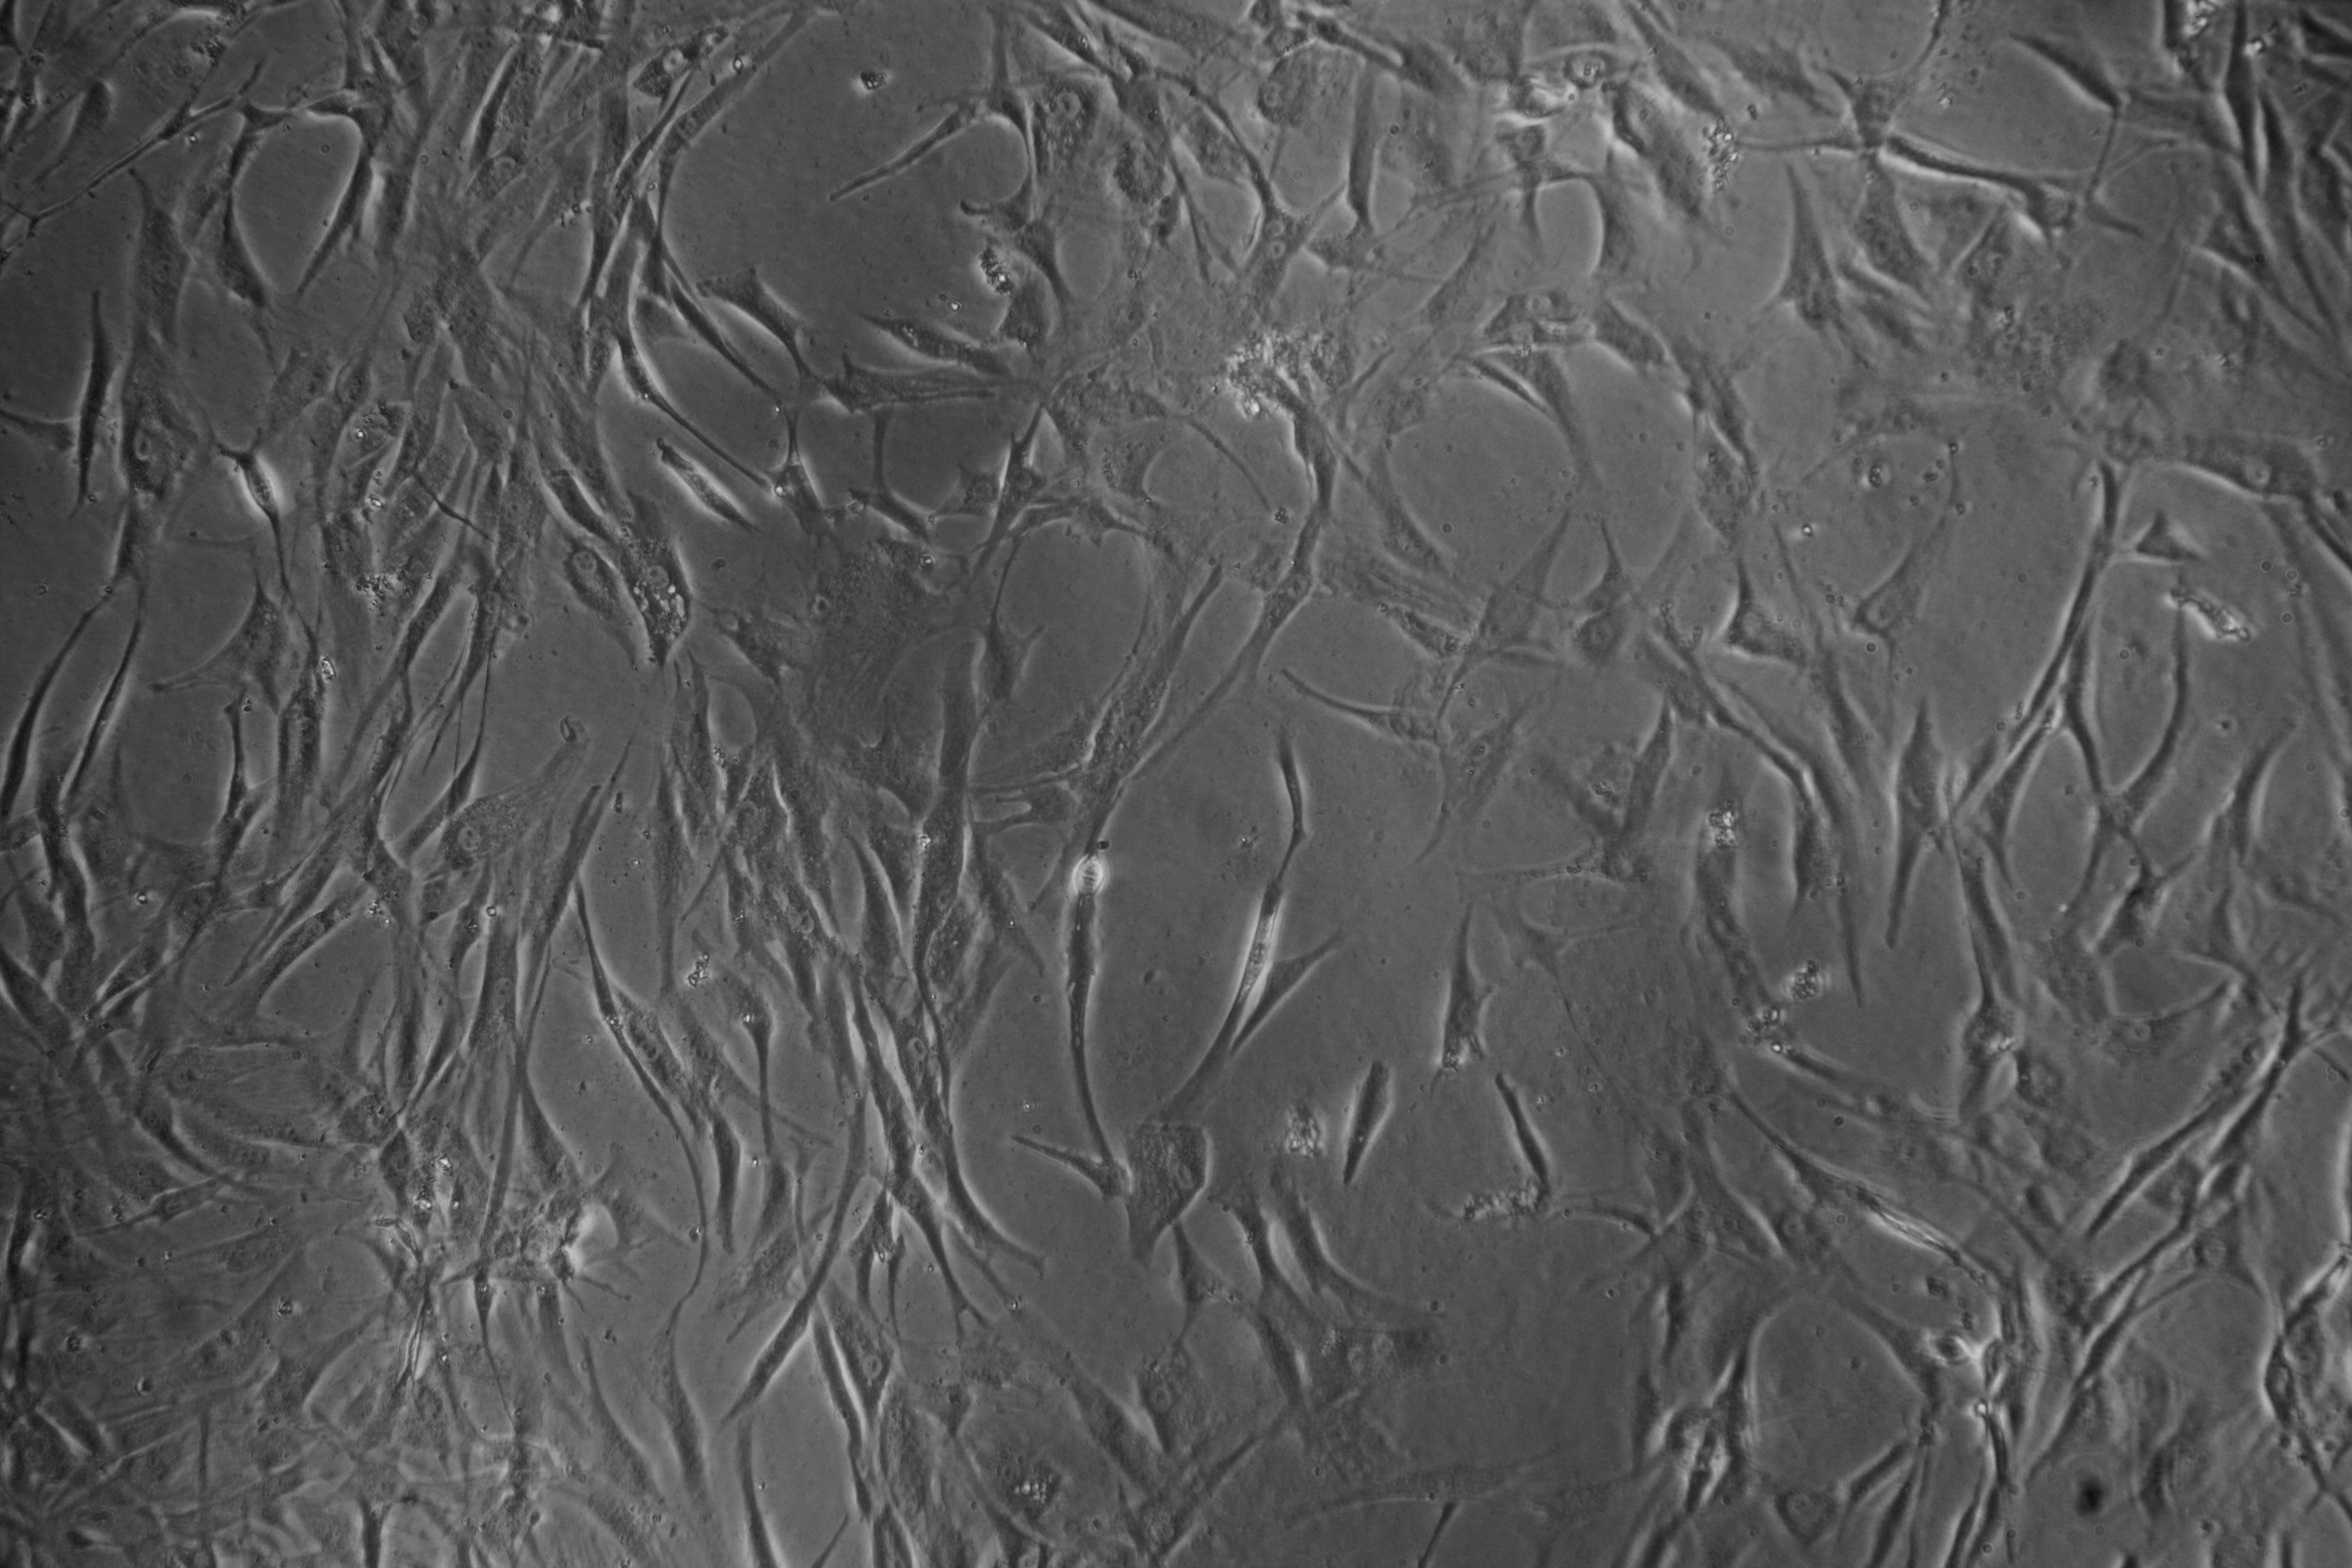

Introducción. Se revisaron los fundamentos biológicos de la medicina regenerativa, en particular de las células madre y de los factores de crecimiento plaquetarios. Se presentan la clasificación, fuentes de obtención y mecanismos de acción propuestos para las células madre, así como los grandes desafíos biotecnológicos para el desarrollo de la medicina regenerativa y la evidencia clínica de su relación seguridad/efectividad en la práctica médica.

Objetivo. Revisar y sistematizar la información actualizada acerca de los fundamentos y potenciales usos de la medicina regenerativa.